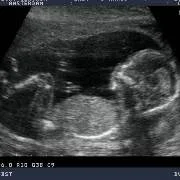

Vandaag was ik samen met mijn vrouw, moeder en neefje bij Dr. Papa. De naam alleen al maakt je vrolijk, dan zie ik mijn kleine mannetje weer op het scherm (oeps heb ik verraden wat het word). Dr. Papa legt alles zo haarfijn uit en het aller mooiste en belangrijkste is dat het kindje alles heeft en alles doet. In 3d zie ik zijn gezichtje en geloof het of niet, ik zie mijn kleine even lachen, mama zegt hij lijkt op jou, de glimlach die ik toen kreeg is er de hele dag gebleven, en nu ik dit schrijf verschijnt hij weer.

Wauw! Wat een bijzonder moment, het zien van ons eerste kindje in 3D! De neus van de een en de kleine krulletjes van de ander die al te zien waren. Te gek!

Vlinders in mn buik Wat een magisch moment toen we voor het eerst het gezichtje van ons kleine wondertje zagen, ze lachte en deed haar oogjes open, alsof ze naar ons gluurde. Dit is echt geweldig, nog helemaal aan het nagenieten. Ik kan iedere a.s. ouder Dr. papa aanbevelen.Hij geeft zeer heldere uitleg en heeft veel geduld en liefdevolle aandacht.

Vandaag onze nu al fantastische dochter gezien in 3 & 4D. Een magisch moment, want nu hebben we écht duidelijk beeld bij haar lieve, mooie snuitje en dat beweeglijke lijfje. Dat wat ik voelde is nu samengekomen met dat wat we van haar gezien hebben. Een waanzinnige ervaring! Heel veel dank dr. Papa, ook voor de heldere, begeleidende uitleg!